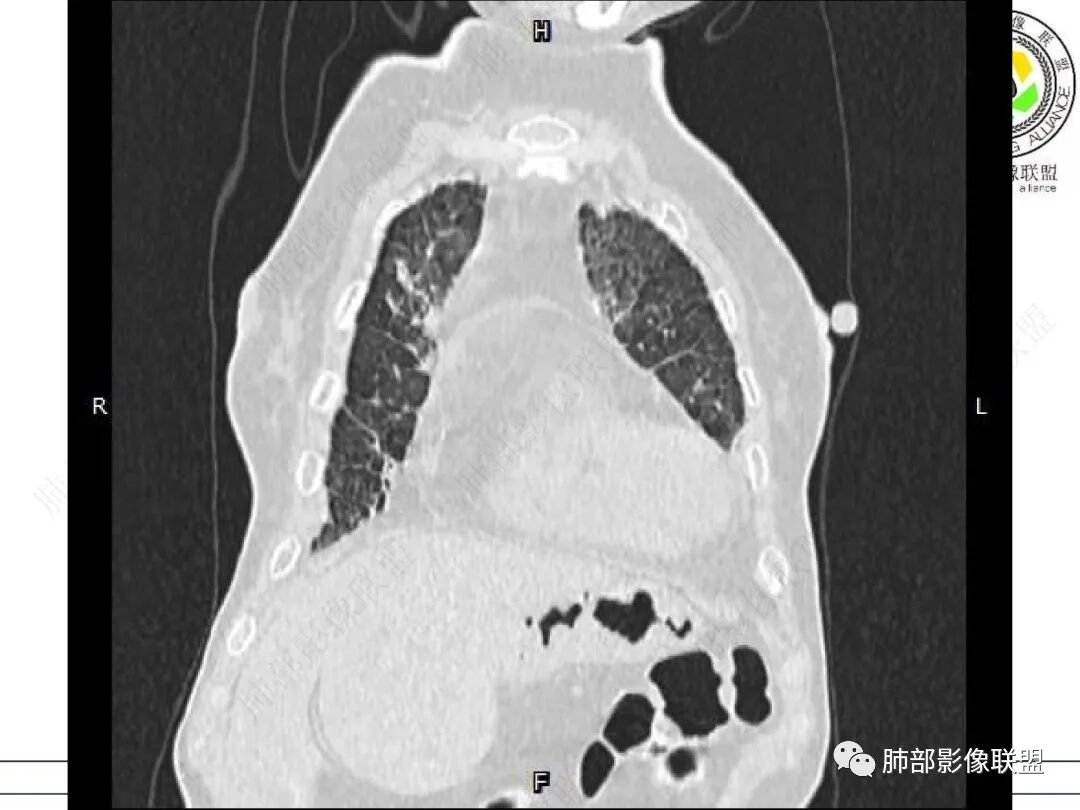

女,71,外阴疼痛2周,发热1周。类风关、高血压、高血糖、卵巢囊肿、肠粘连、胆囊结石等病史及相关药物治疗史。胸部CT:两肺弥漫磨玻璃,血管束增粗,两下肺后肋膈角多发蜂窝,对称分布,双侧胸腔少量积液,纵隔窗心脏大血管影明显增宽。考虑混合性病变,CTD-ILD,并肺水肿?并PJP?。

GGO重力趋势明显,PJP重力趋势没这么明显

GGO重力趋势明显,双侧胸腔积液,还是比较支持肺水肿类病变。

①影像表现复杂:较弥漫间质性改变,对称磨玻璃密度为主,小叶间隔增厚,有一定重力分布趋势,未见明显纤维化,气囊及蜂窝位于肺边缘,未见典型“月弓征”。心脏影增大,双侧胸腔积液。

患者存在肺水肿应当是合理的解释。其他旁证还有,心脏影增大,肾小球滤过率降低,双侧胸腔积液等等……